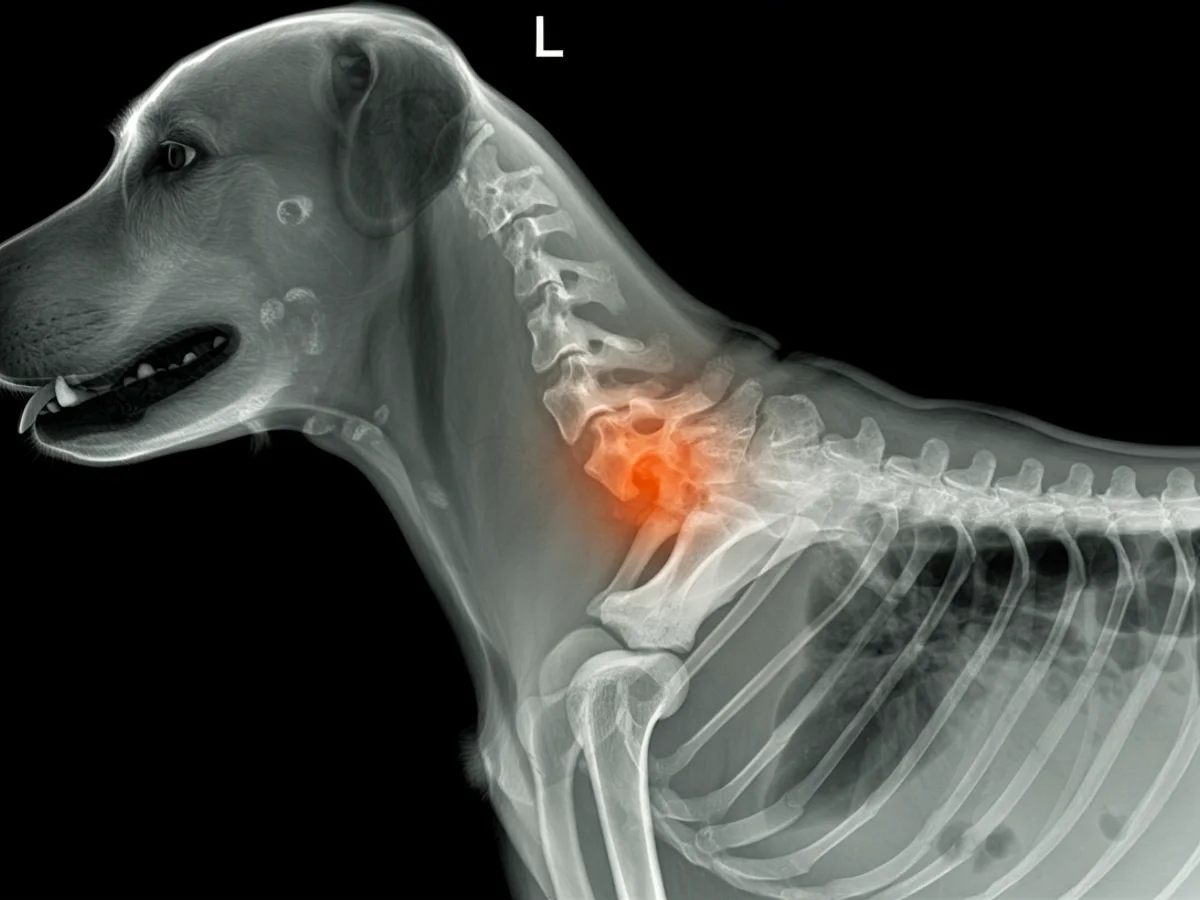

Ein **Bandscheibenvorfall** beim Hund tritt auf, wenn die Bandscheiben degenerieren und auf das Rückenmark drücken. Diese Erkrankung kann besonders bei bestimmten Rassen wie Dackeln oder Französischen Bulldoggen häufig vorkommen. Er kann zu starken Schmerzen, Mobilitätsverlust und sogar Lähmungen führen. **Schnelle tierärztliche Behandlung** ist entscheidend, um bleibende Schäden zu vermeiden. Für jeden Hundehalter ist es wichtig, die Symptome zu kennen, um rechtzeitig handeln zu können.

Zur Diagnose eines Bandscheibenvorfalls wird der Tierarzt zunächst eine körperliche Untersuchung durchführen. Dabei wird der Hund auf Schmerzreaktionen und neuromuskuläre Defizite überprüft. Ergänzend dazu können bildgebende Verfahren wie Röntgen, MRT oder CT eingesetzt werden, um den genauen Zustand der Bandscheiben und das Ausmaß des Vorfalls zu bestimmen.